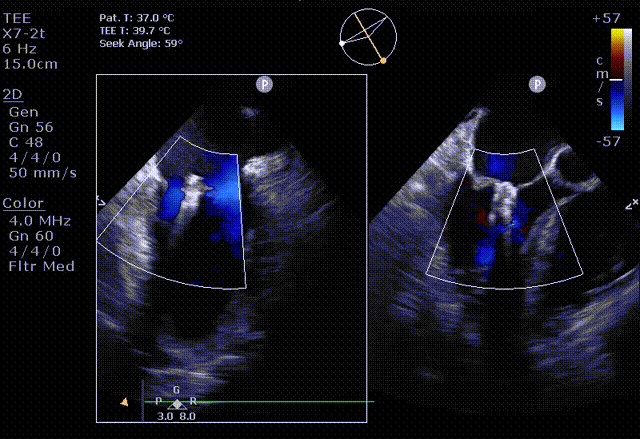

在阜外医院潘湘斌教授团队的支持下,手术经股静脉-房间隔入路,采用全身麻醉插管,在TEE和DSA引导下完成房间隔穿刺。置入JensClip瓣膜夹系统后,在左房调整瓣膜夹的位置和轴向,后进入左室,在TEE引导下捕捉二尖瓣前后瓣叶,并关闭瓣膜夹。经TEE反复确认手术效果后最终锁定并释放瓣膜夹。术后即刻超声显示瓣膜夹位置稳定,功能良好,二尖瓣反流由术前4+减少至微量,手术圆满成功。

术后超声